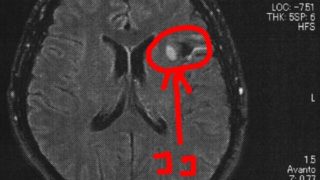

GLIOMA:手術後51ヶ月目の検査

半年ごとの定期検査のために久しぶりに病院に戻った。2014/6/23の覚醒手術から約51か月になる。MRI検査の結果、半年前と比べても変化は無いように見えるが、一年前やそれ以前の画像と比べると若干変化があるようにも見える。と先生が言う。今回...